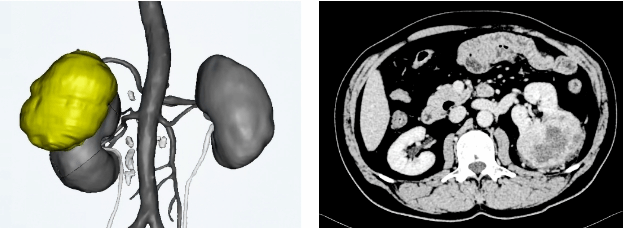

入院后,在进一步的检查中发现患者病情比想象中要严重,评估发现患者左肾肿瘤大小约10x8cm,并且肺多发结节,部分肺结节考虑转移病灶可能,遂组织胸外科专家会诊评估,建议优先处理肾脏肿瘤,待患者恢复后行肺结节手术治疗。根据最新中国泌尿外科指南,针对一般状况良好,手术能显著降低肿瘤负荷的转移性肾癌患者,可行减瘤手术,并进行辅助治疗,可使得患者有较长期的生存,也得到了多项回顾性研究的证实。为患者能最大限度获益,建议行肾脏减瘤手术,本次手术由方针强教授主刀,各学科极力做好保障。

术前,新桥医院泌尿外科中心方针强教授、李佳主治医师,和紧张而焦虑的患者及家属进行充分沟通,提前做好各种应急手术预案。因患者左肾肿瘤较大,目前针对泌尿外科指南推荐:小于4cm肾肿瘤,优先选择行肾部分切除术,大于4cm肾肿瘤,根据术者技术水平和经验、所在医院的医疗条件以及患者的体能状况进行综合评估,行保留肾单位的肾部分切除术。患者一般情况好,身体状况可,因肺结节考虑转移性病变,术后需辅助进一步治疗,若患者行肾根治性切除术,术后若患者肾功能异常,对后续治疗可能造成影响,遂在患者及家属的积极配合下,选择行保留肾单位的极限保肾手术。

术中,在麻醉科团队的精心护航下,方针强教授利用丰富的手术经验,精准判断巨大肿瘤深度及复杂肾血管位置,在空间极其狭小的情况下,用他那精湛的手术技艺,顺利进行左肾部分切除术并彻底止血,术中出血不到100ml。患者术后第二天下床活动,仅5天就顺利康复出院。术后病理提示:“(左肾肿瘤)恶性肿瘤,结合形态学及免疫表型支持肾细胞癌,切缘无肿瘤”。